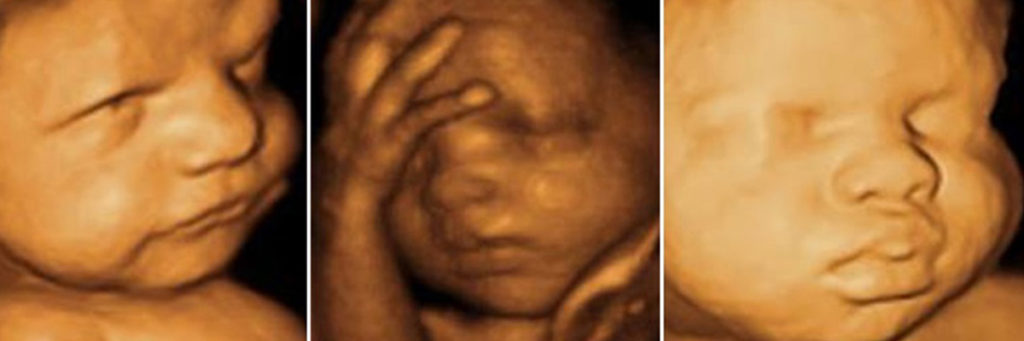

Obstetrik ultrason – Gebelik Ultrasonu

Obstetrik ultrasonu, gebelik takiplerinde yapılan ultrasona verilen isimdir. Cihaz fetüse ve eklerine ait görüntüleri monitöre yansıtır yansıyan bu görüntüler ekranda incelenir. Ultrason cihazı ana gövde, pror (transuder), monitör, kamera ve printerden oluşur. Ultrasonun temel amacı dokuya temas eden proptan yayılan ses dalgaları değişik dokulardan değişik oranlarda ve tonlarda yansıyarak alıcıya geri döner. Bu yansımalar, bilgisayar ortamında işlenip görüntüye dönüşür. Bu görüntülere bakarak organların normal yada patolojik olup olmadığına karar verebilir.

Ultrasonografi fetüsün değerlendirimesinde adeta vazgeçilmez tanı aracıdır. Gücenli ,etkili ve ucuz bir yöntem olarak kabul edilir. Ultrason 18-22. Gebelik haftaları arasında bebeğin tüm organ ve dokularının ayrıntılı incelenmesi olanağı verir. Bu dönemde yapılan renkli ultrason , ikinci düzey tarama, detaylı , ayrıntılı terimlerin hepsi aynı anlamı ve işlemi ifade etmektedir.

Detaylı ultrasın fetüsün tüm organ ve dokuların gelişmesini tamamladığı 18-22. Haftalarda yapılır. Zira bu dönemde saptanan anomalilerde gebelik sonlandırılması açısından tıbbi olanak sağlamaktadır.

İyi cihazlar kullanılmasına detaylı tarama yapmayı, deneyimli ultrasonografist olmasına rağmen doğuma bağlı kusurların ancak %70-80’i fark edilebilir. Ayrıntılı tarama 18-22 . gebelik haftalarında çözünürlüğü yüksek , 3. Kuşak gelişmiş cihazlarla ile 15-20 dakika içerisinde tamamlanır.